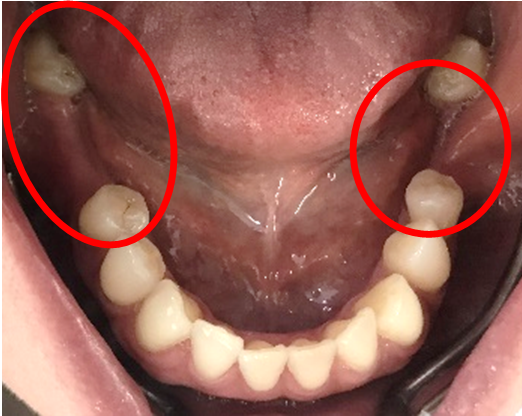

男性Kさん 50代(インプラント)

主訴

歯がグラグラするところ、むし歯のところ、しみるところ、被せ物がとれたところ、歯茎が腫れて血が出るところ、歯が抜けているところがある。すべて治したい。

治療内容

残っている歯を抜歯し、上下インプラント治療をしました。

所感

歯周病が進行している歯、むし歯が進行している歯がほとんどで、レントゲンを撮り、詳しく診てみると、ほとんどの歯を保存することができないことがわかりました。抜歯後は、入れ歯かインプラントの方法があります。治療開始前に患者さんに詳しく現状を説明し、治療法についてじっくり相談しました。自分の歯と同じような感覚で食事できるインプラント治療を選択されました。治療後、表情がとても明るくなり、口元がとても自然で10歳以上若返ったように感じました。「時間はかかりましたが、インプラントにして本当に良かったです!」と素晴らしい笑顔でお話ししてくださいました。

上顎:¥3,280,000(税込)

下顎:¥3,280,000(税込)